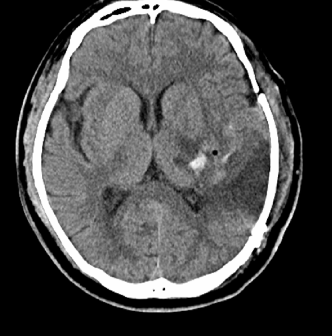

手术做的很顺利 , 病人回到了监护室 , 手术后的CT复查也让手术医生以及季医生非常满意 。 小童看着术后的片子 , 感觉大脑痛苦的表情也有所缓解 。

文章图片